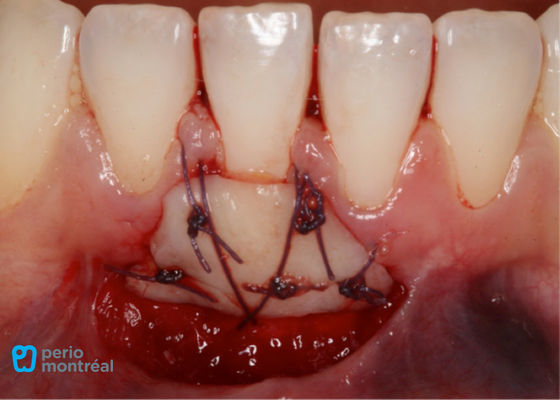

The recipient site is prepared following root planing of tooth #41 to decrease the root convexity. The donor tissue is harvested from the right palate.

Graft Sutured at Recipient Site, Palate Treated with a Hemostatic Agent and Sutured